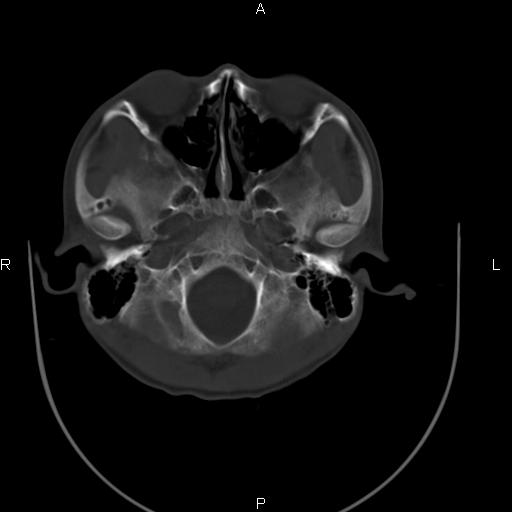

标题: CT27115:大家看一看,这孩子的颅骨表现?

两名中学生打架,脑质内未见异常,未上传。

两例——颅骨结构正常,未见明显骨折征象。

感觉第2个颅缝密度高,额顶部板障有点厚,正常变异?地中海贫血?